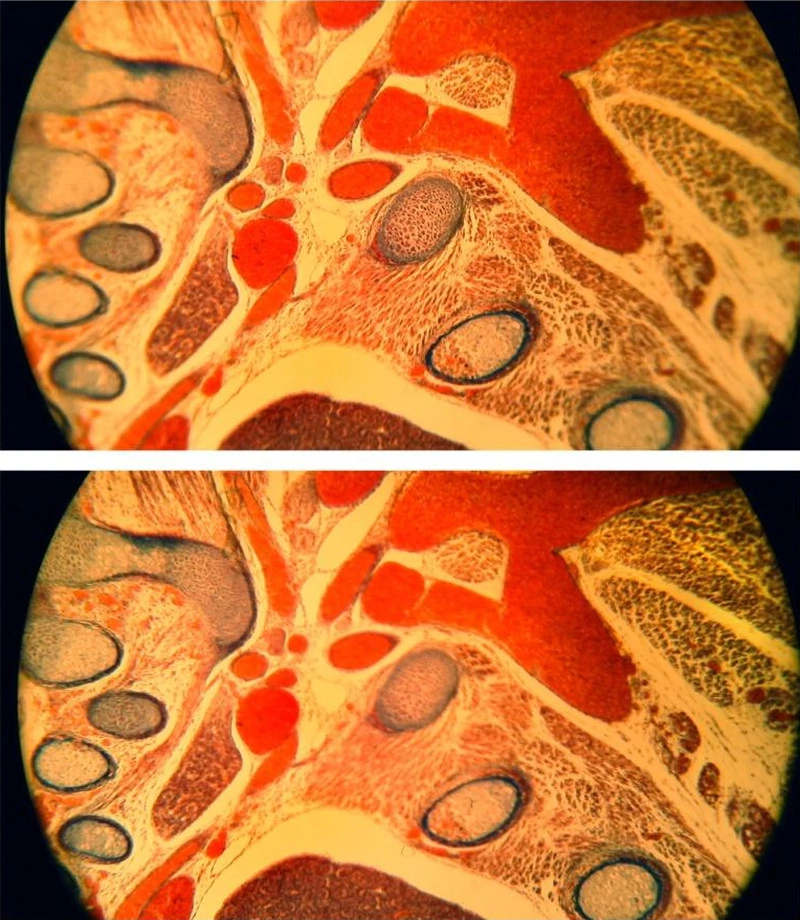

在這種情況下,具有明顯邊緣柔化的非平面校正物鏡(簡易的消色差物鏡)可用來進行測試,且顯微鏡可持續對焦樣本,或可選擇將自動對焦設定對準觀測區域的中心或周圍(圖 12)。儘管手動調整聚焦面,而不調整焦距,選擇性自動對焦仍可讓人輕易對周圍重新對焦和觀測螢幕影像上的任一有趣細節。